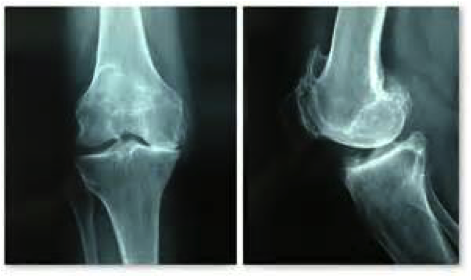

Le diagnostic

Le diagnostic de rupture du ligament croisé antérieur (LCA) peut être évoqué dès l’accident.

Il est habituellement affirmé par l’examen clinique.

Quels sont les examens complémentaires nécessaires ?

Les examens complémentaires vont confirmer le diagnostic, et faire le bilan de lésions associées (ménisques, lésions ligamentaires) :

- Bilan d’imagerie : IRM, Arthroscanner.

- Laximétrie (appareil spécifique d’aide au diagnostic, et de suivi).